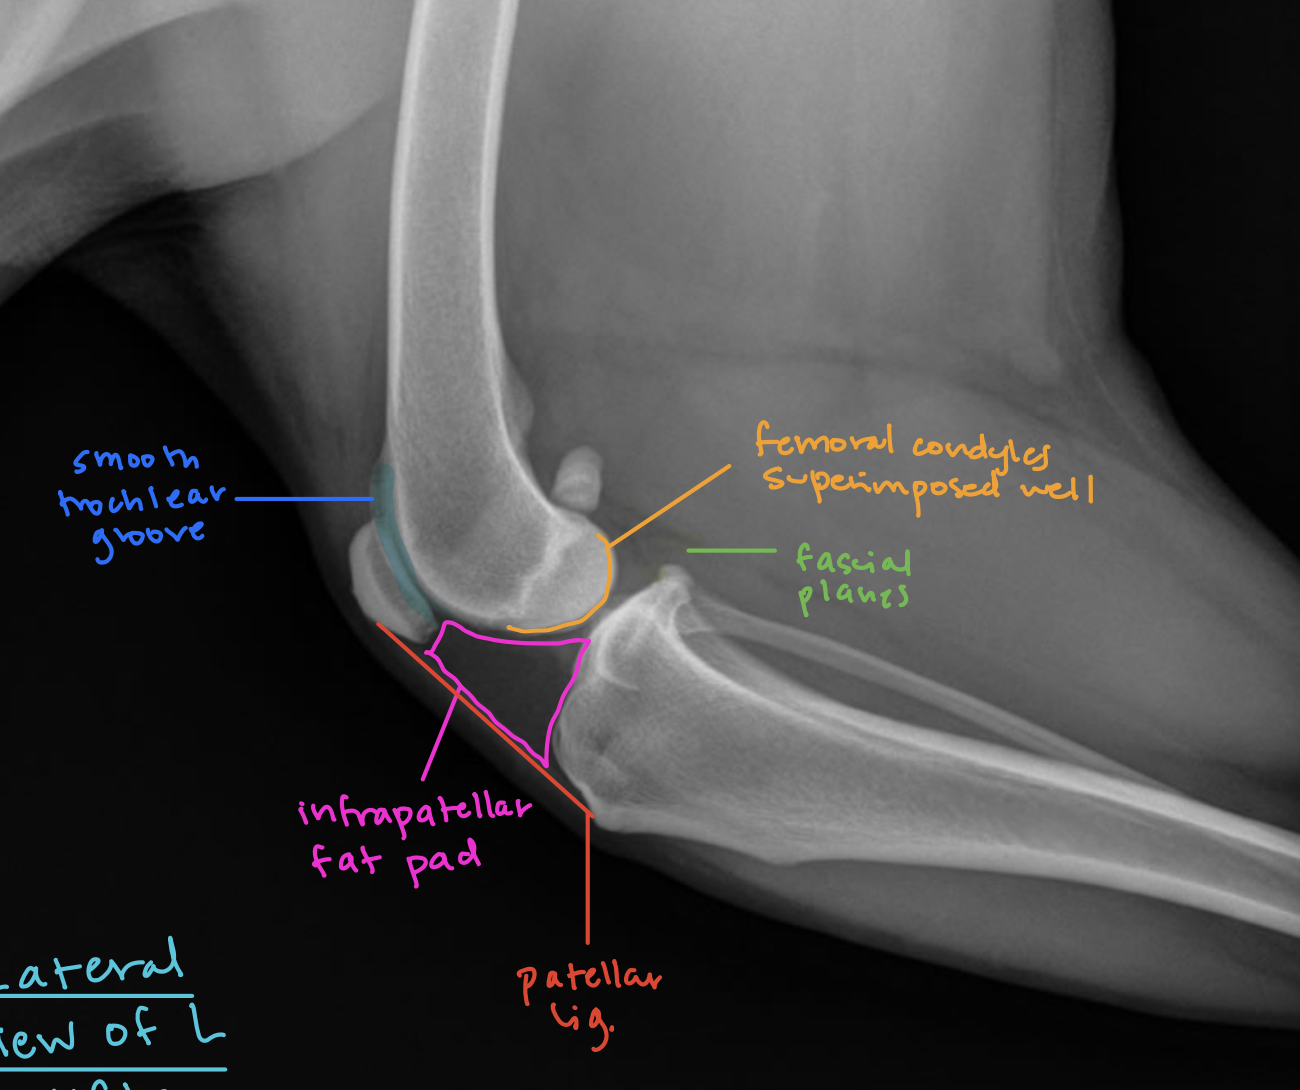

Label the following colored structures

A

blue: smooth trochlear groove

pink: infrapatellar fat pad

red: patellar ligament

green: fascial planes

orange: femoral condyles